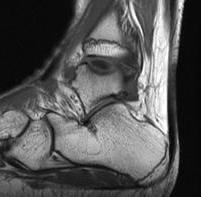

MRI

Stable lesion (Stage I) - cartilage intact, no synovial fluid under lesion

Unstable lesions (Stage II or III) - cartilage breach, synovial fluid under lesion

Displaced lesion with resultant osteochondral defect

Stable lesion with intact cartilage and no synovial fluid under lesion

Stage III completely detached but not displaced